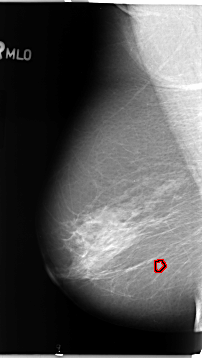

B_3098_1.LEFT_MLO

LEFT_MLO LINES 4680 PIXELS_PER_LINE 2720 BITS_PER_PIXEL 12 RESOLUTION 50 NON_OVERLAY

FILE: B_3098_1.RIGHT_MLO.OVERLAY

TOTAL_ABNORMALITIES 1

ABNORMALITY 1

LESION_TYPE MASS SHAPE IRREGULAR MARGINS ILL_DEFINED

ASSESSMENT 4

SUBTLETY 3

PATHOLOGY BENIGN

TOTAL_OUTLINES 1

BOUNDARY